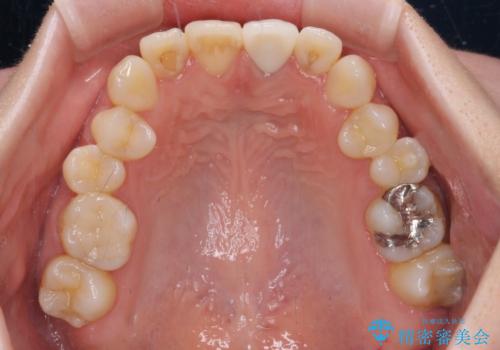

- 前歯のクラウン付近の歯肉が黒く見えることを気にして来院された患者様です。

根管治療を行った後に、オールセラミッククラウンにて補綴することとしました。

オーダーメイドタイプのクラウンを選択いただいたので、まるで天然の歯と見間違うほど自然に仕上がり、患者様には大変満足していただきました。